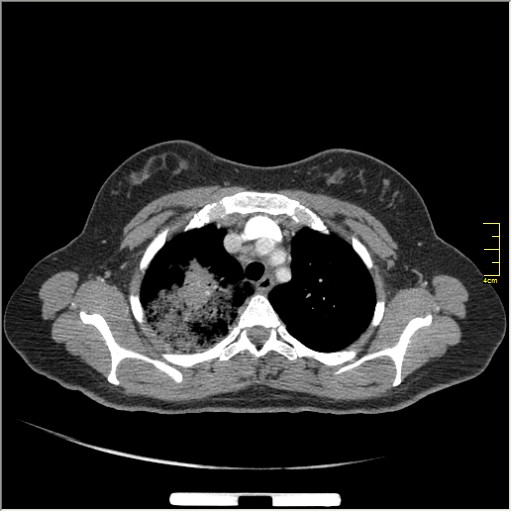

Далее рекомендуем лабораторные исследования, КТ легких.

KT

Давайте определимся, для начала обозначим какие КТ признаки мы видим на представленных сканах. И главное это не перечисление вариантов диагнозов (если нет однозначного варианта); а определить что надо сделать следующим этапом для достижения окончательного диагноза.

Вполне адекватная тактика. КТ контроль через 3-4 недели после антибактериальной терапии, совершенно правильно.

В данном случае, пульмонолог решил пойти на бронхоскопию; был забор материала. Лабараторный анализ (ПЦР) выявил положительную реакцию на туберкулёз.